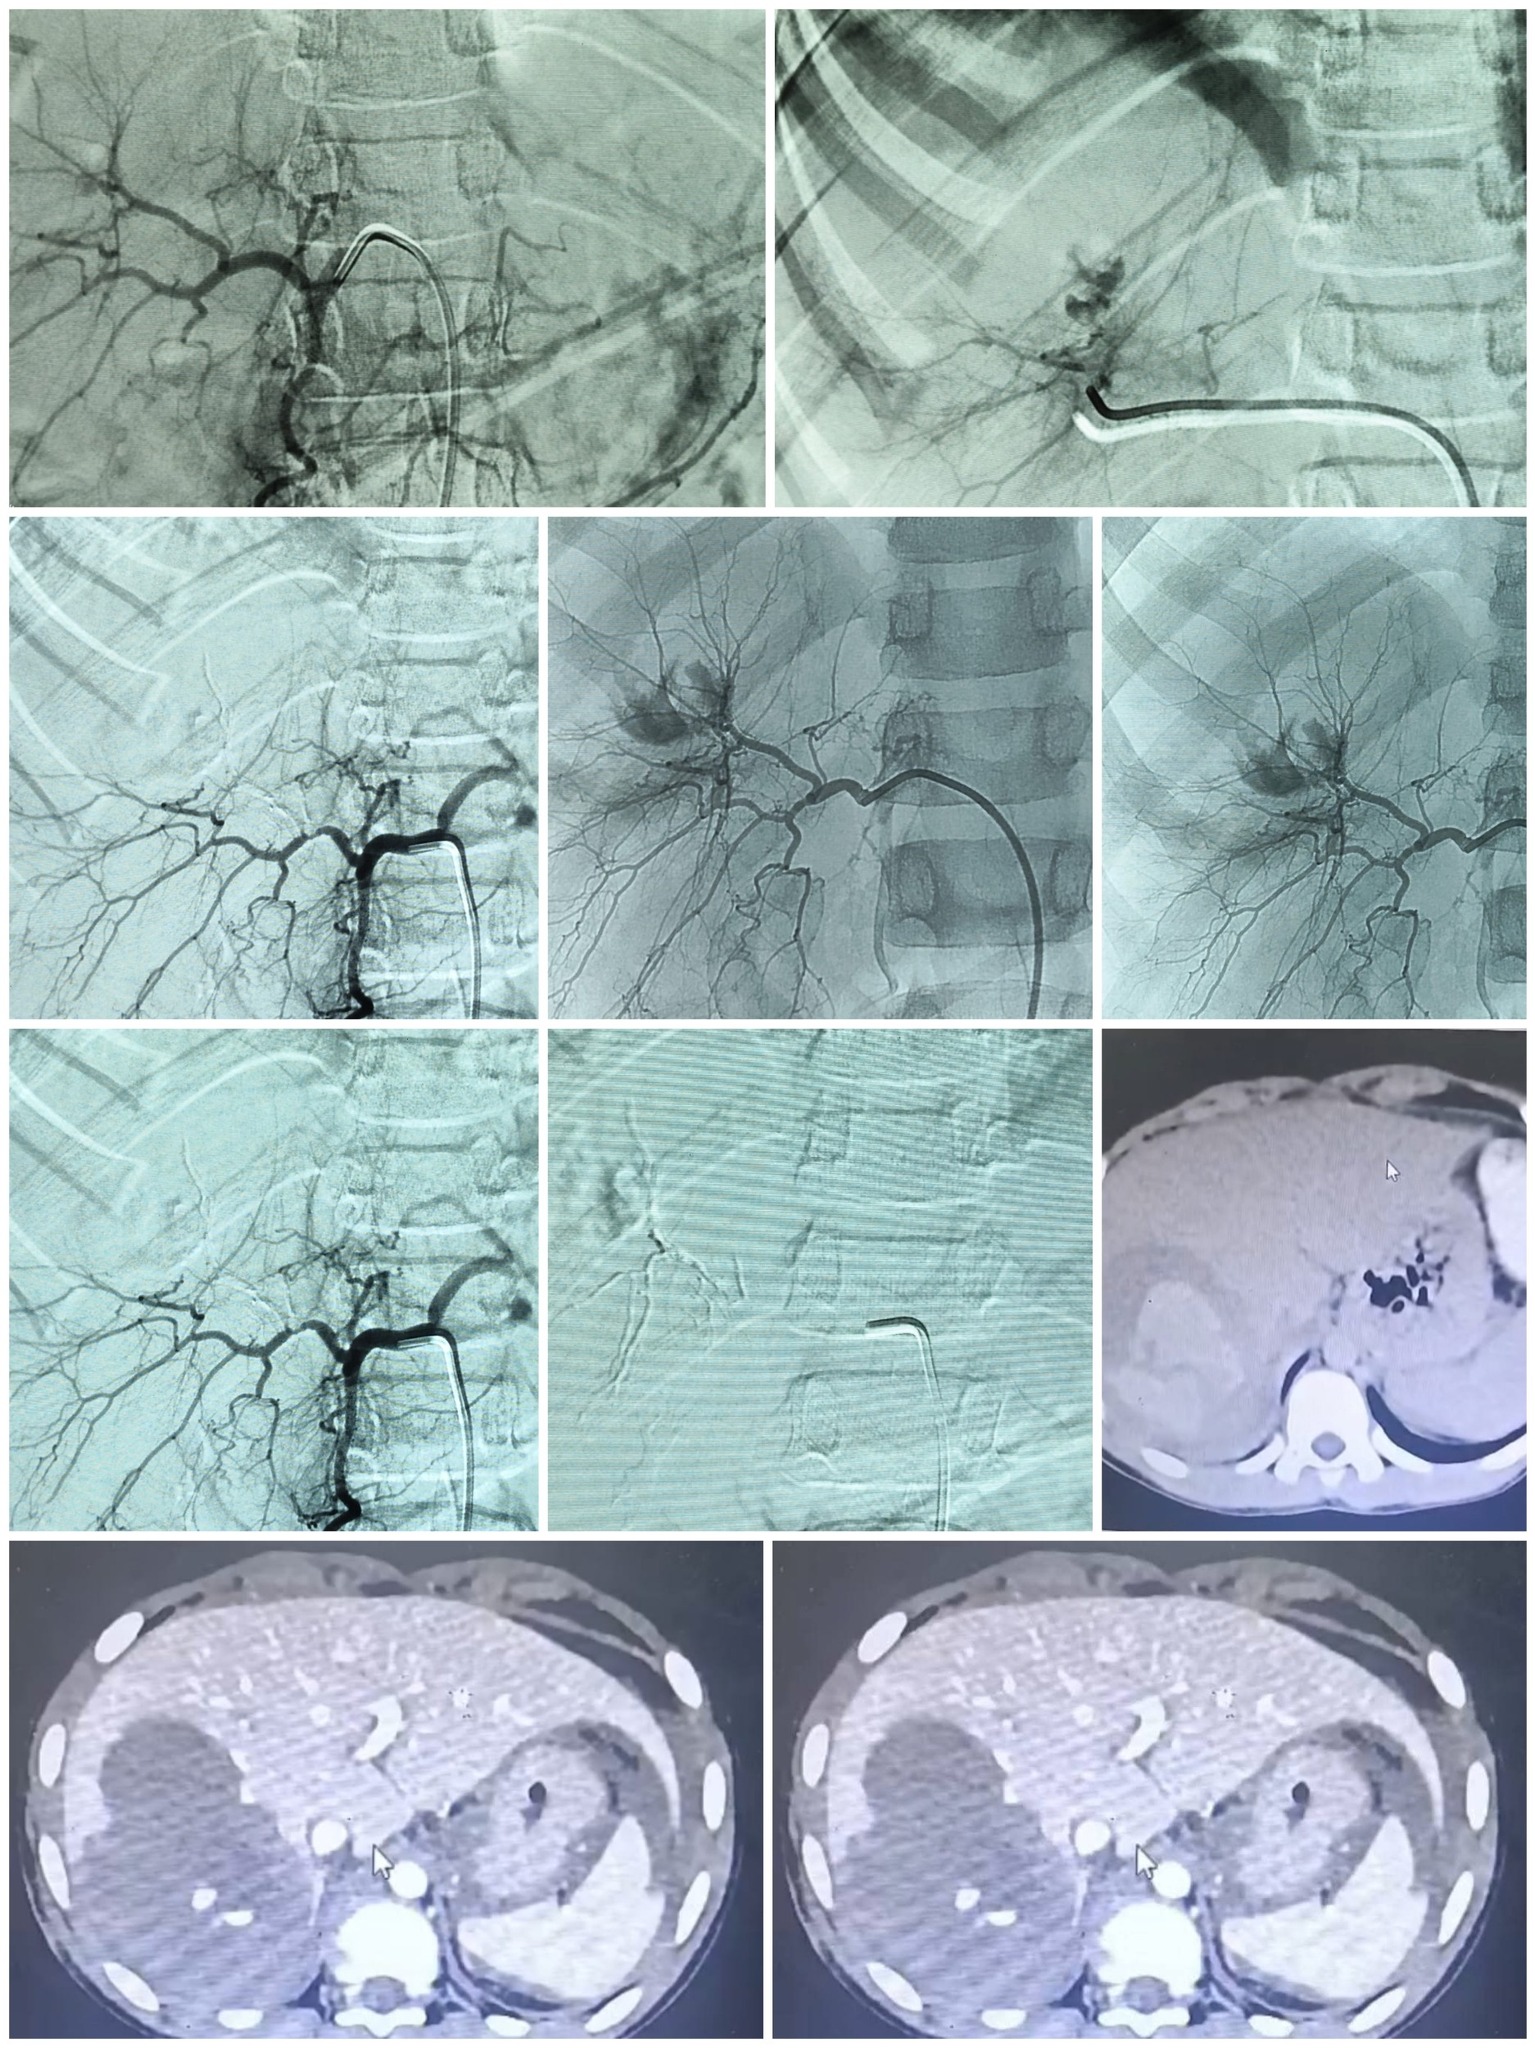

في إطار النجاحات المتواصلة التي تحققها الفرق الطبية المتخصصة بمستشفيات جامعة أسيوط، تمكن فريق طبي بقسم الأشعة التشخيصية والتدخلية والتصوير الطبي، من إنقاذ حياة طفل يبلغ من العمر ١٢ عاما، تعرض لإصابات بالغة ونزيف حاد في الكبد إثر حادث سير، جاء ذلك تحت رعاية الأستاذ الدكتور أحمد المنشاوي، رئيس الجامعة، والأستاذ الدكتور علاء عطية، عميد كلية الطب ورئيس مجلس إدارة المستشفيات الجامعية.

كان المستشفى الإصابات برئاسة الأستاذ الدكتور محمد عبد الحميد، قد استقبل طفل مصابا بإصابات متفرقة بعد حادث كان يقود فيه دراجة نارية "موتوسيكل"، ويعاني من تمزق حاد في الكبد أدى إلى قطع شرياني ونزيف داخلي عنيف ومهدد للحياة.

استدعى الوضع تدخلا سريعا ودقيقا، حيث يتم نقل المريض للمستشفى الرئيسي برئاسة الأستاذ الدكتور خالد عبد العزيز، ليقوم الفريق الطبي بقسم الأشعة، الذي جاء تحت إشراف الأستاذ الدكتور حسن إبراهيم مجلي، رئيس قسم الأشعة التشخيصية والتداخلية، والأستاذ الدكتور مصطفى هاشم، أستاذ الأشعة التشخيصية والتداخلية، وضم كل من الدكتور حمدي محمد إبراهيم، أستاذ مساعد الأشعة التشخيصية والتدخلية، والطبيب مصطفى طارق خلف الحسيني، أخصائي الأشعة، عاونهم الطبيب أحمد محمد حسين، طبيب مقيم بقسم الجراحة، والطبيب عمر المختار عبد العزيز، طبيب الطوارئ، ومن هيئة التمريض الأستاذ شعبان رمضان، والأستاذ عماد ناصح، فني بقسم الأشعة، استخدام تقنية القسطرة الشريانية التداخلية، وهي إجراء يتطلب مهارة عالية ودقة متناهية، وقد نجح الفريق في تحديد موقع النزيف الشرياني وإيقافه بشكل، مع الحفاظ التام على سلامة باقي الشرايين المغذية للكبد، ليعلن الفريق الطبي عقب ذلك استقرار حالة الطفل.

يعد هذا الإجراء من التدخلات الطبية المتقدمة التي تجنب المريض الجراحة المفتوحة المعقدة والمحفوفة بالمخاطر في حالات النزيف الحاد.